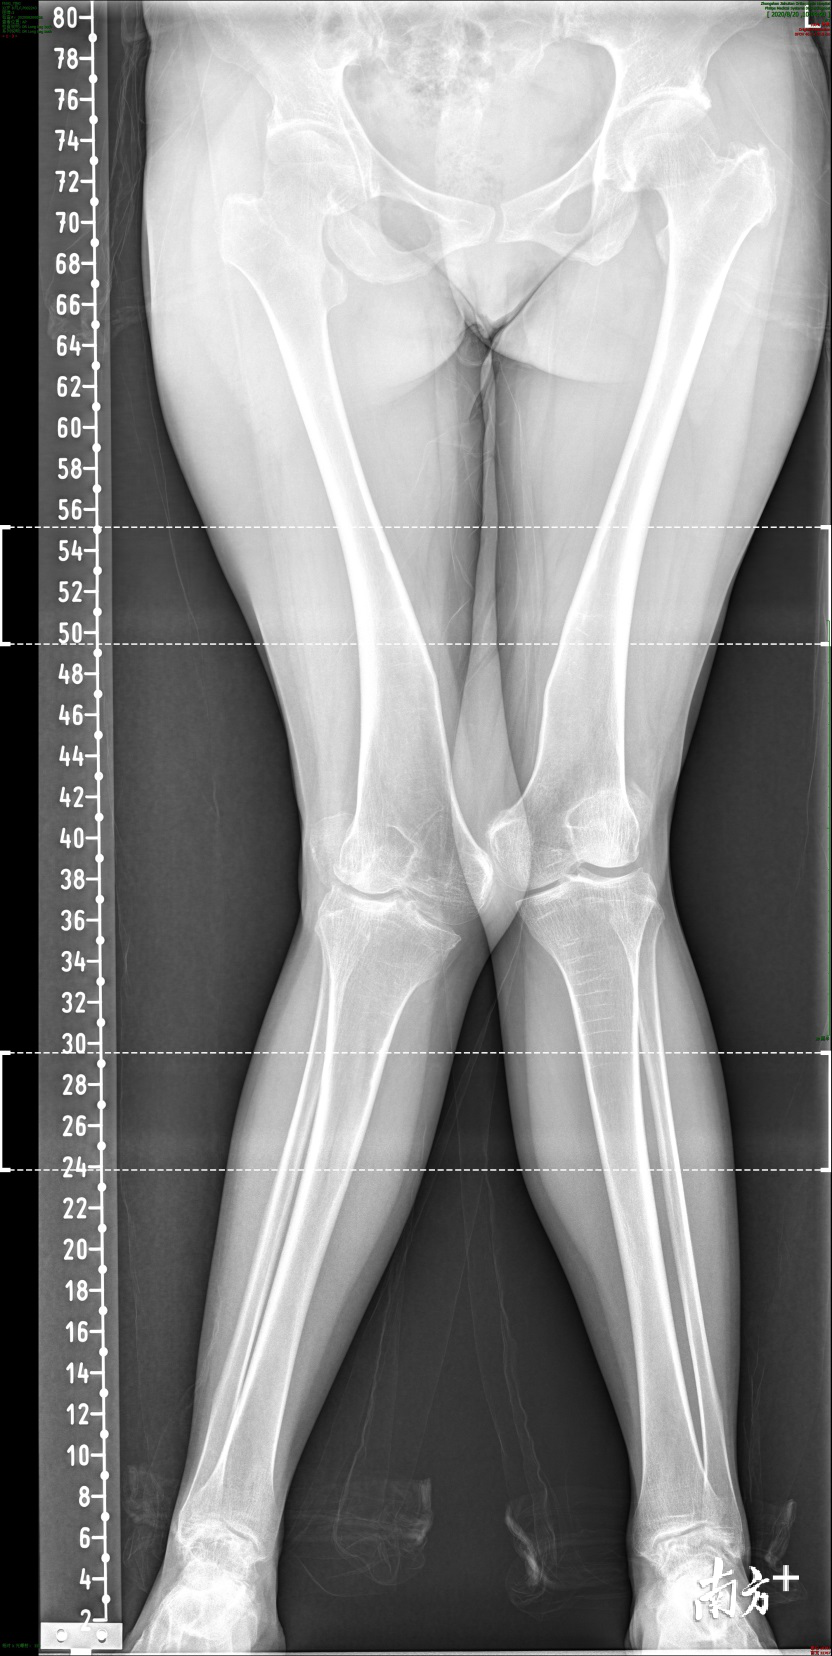

据中山积水潭骨科医院透露,自7月1日,“骨科爱心行”公益手术开幕以来,医院接收到了数名患者报名。而开展第一台“骨科爱心行”中山地区公益手术的患者——冯女士是中山人,患有后天性膝外翻,就是我们通常所说的“X”形腿,虽然才30多岁,但已忍受病痛20余年。

后天性膝外翻,就是我们通常所说的“X”形腿。

20多年来,冯女士双膝关节外翻逐渐加重,现在两个脚之间距离已经快达到30cm,不仅步态不正常,走多了腿就累就疼,严重影响日常生活,很是困扰。为了治疗,冯女士花光了大部分的积蓄,去到各个地区寻访医生,但因为面临手术的难度较大、医疗费用昂贵的压力,冯女士二十多年来一直强忍病痛,无力去医院诊治。

手术从上午九点到下午两点,持续了6个小时,此次手术由中山积水潭医院执行院长姜旭及院内骨科团队参与,采取的截骨矫形钢板内固定术式,从截骨位置、截骨角度等经过周密的术前设计,术中顺利在畸形最大位置进行截骨,矫正位置后,钢板固定,成功矫正了冯女士右下肢外翻畸形。